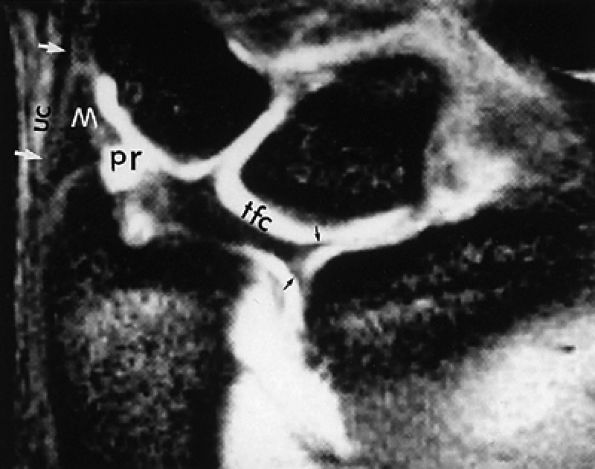

FIGURE 10.1 ● A 3D fast spoiled GRASS (FSPGR) with intra-articular contrast injected into the radiocarpal compartment. The torn lunotriquetral ligament (straight arrow) allows extension of contrast into the midcarpal compartment and the torn radial attachment of the TFC (curved arrow) directs contrast into the distal radioulnar joint. Note the superior trabecular bone detail on this image (coronal image; TR, 40.4 msec; TE, 14.5 msec; FOV, 4 cm; slice thickness, 2.0 mm; matrix, 512 × 256; flip angle, 30°).

FIGURE 10.69 ● A T2*-weighted image showing the TFC complex. Black arrows, radial attachments of TFC; white arrows and UC, ulnar collateral ligament; M, meniscus homologue; pr, prestyloid recess.